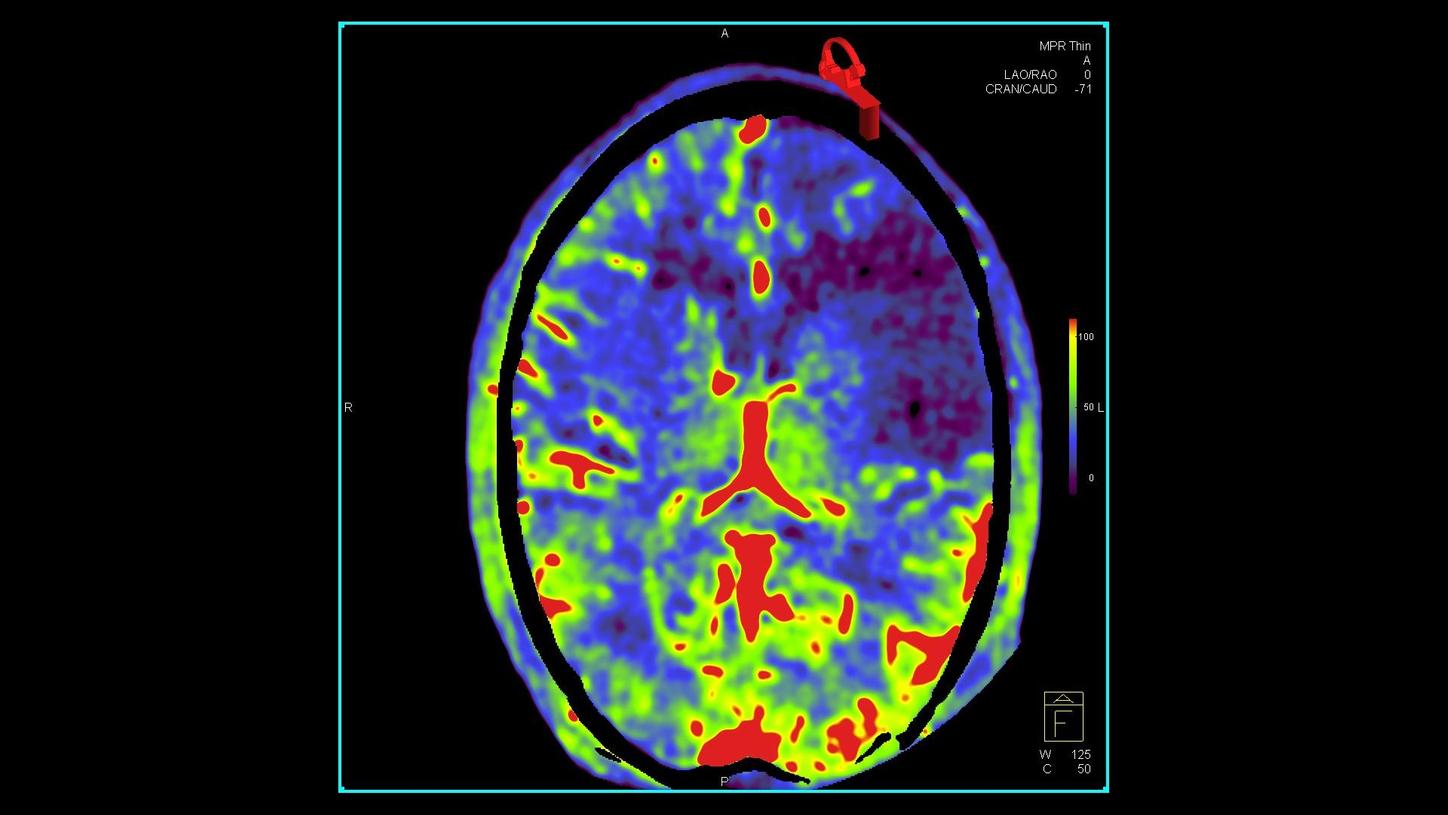

OPTIQ for interventional radiology

A new approach to image quality and dose in minimally invasive interventions

During a procedure, interventionalists and surgeons have to see clearly – while keeping dose as low as possible. Based on big data, OPTIQ delivers constant image quality throughout a procedure, independent of angulation or patient size1,2, while also significantly reducing dose.

Find out more about OPTIQ and how it supports you in expanding precision medicine.